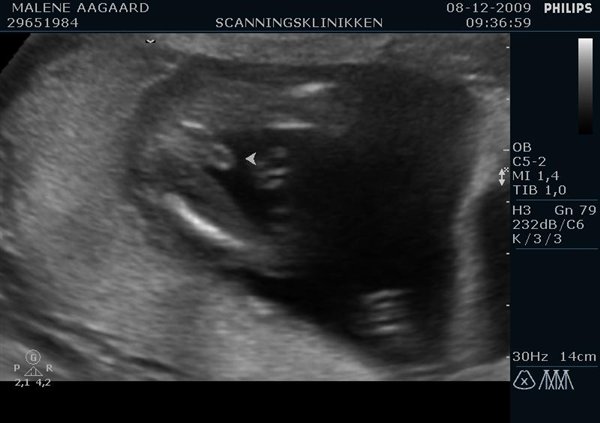

Som inspiration fra en anden tråd herinde, ville jeg hører om i har billedet, der beviser, at det enten er en dreng eller en pige?

Jeg tænker tit på, om skanningsdamen så rigtigt, og måske vi kunne sammenligne ?